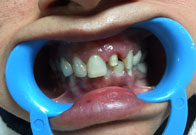

(10) Dental Implant - Full Mouth

Before Treatment

After Treatment

Patient came with a problem in chewing food and multiple loose teeth in upper and lower jaw and was interested in getting a whole new set of teeth in both the jaws. So after removal of all the weakened teeth and placement of multiple implants, he was given implant supported bridge.